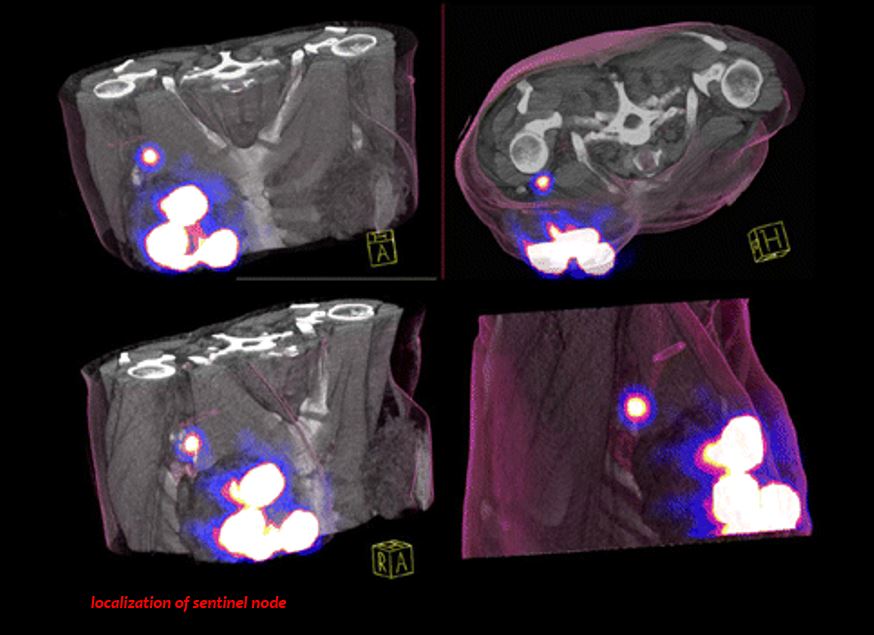

¿Cómo se aplica? En pabellón se inyecta el elemento radioactivo cerca del tumor y se puede ver como “viaja” hasta el ganglio, lo que permite detectarlo, marcarlo e intervenirlo. Y si se complementa con el uso de la gamma cámara SPECT CT, única en la región en un hospital público y una de las pocas que existen en el país, se puede definir con mayor precisión la ubicación del ganglio en el cuerpo. Una biopsia determinará si la estructura está sana o tiene rastros tumorales, lo que en ese caso, implicará la remoción de otros ganglios.